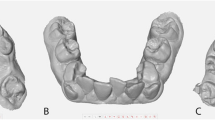

Manual diagnostic setup

The pretreatment study models were duplicated using alginate (Hydrogum 5, Zhermack, Italy) impressions of the upper and lower arch models, following the manufacturer’s instructions. The duplicates were poured after 30 min, a timeframe validated for high accuracy in studies by Rohanian et al. [23] and Aalaei et al. [24].

The duplicated pretreatment study models were scanned using a 3Shape R-750 desktop scanner (3Shape, Copenhagen, Denmark). Subsequently, they were mounted on a mean value articulator and cut to fabricate a manual orthodontic diagnostic setup, following the method demonstrated by Araújo et al. [2]. The study protocol specified that if teeth were severely damaged, the entire setup process would be repeated, starting from the duplication of the original orthodontic study models, followed by 3D scanning and preparation of the new duplicated models. Notably, no repetition was required for any of the cases during the study. The number and type of broken teeth were recorded for later analysis.

Both manual and digital diagnostic setup protocols were initiated by positioning the lower incisors in their end-of-treatment desired locations, guided by mandibular biological limits, lateral cephalometric radiograph findings, and the treatment plan. The alignment of the lower arch was performed while preserving the pre-treatment lower arch form, a strategy recommended by Kesling [3], Little [26], and Saifeldin et al. [27] to ensure stable orthodontic treatment outcomes.